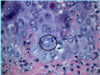

A: Describe Histology (3)

B: Dz

C: What’s the primary leukocyte in the skin

A: image

-Solar Elastosis=Grayish-bluish color of the Dermis from sun damage

B: [Actinic Keratosis-PreMalignant]

C: Lymphocyte

A: Describe Histology (3)

B: Dz

C: What’s the primary leukocyte in the skin

A: image

-Solar Elastosis=Grayish-bluish color of the Dermis from sun damage

B: [Actinic Keratosis-PreMalignant]

C: Lymphocyte